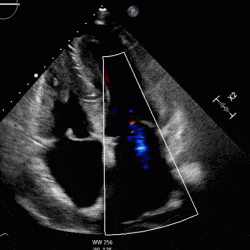

Mr Case Cardio Guide Acc produces clinical guidelines and policy to support clinicians, researchers, and policymakers in delivering high quality cardiovascular care. The document provides guidance on obtaining standard echocardiogram views for anesthesia point of care ultrasound, including the parasternal long axis (plax), parasternal short axis (psax), and apical 4 chamber (a4c) views. These guidelines, which are based on systematic methods to evaluate and classify evidence, provide a foundation for the delivery of quality cardiovascular care. We publish guidelines and related resources to support everyone involved in cardiovascular care. based on our guidelines, these documents explain diagnosis and treatment recommendations backed by evidence.